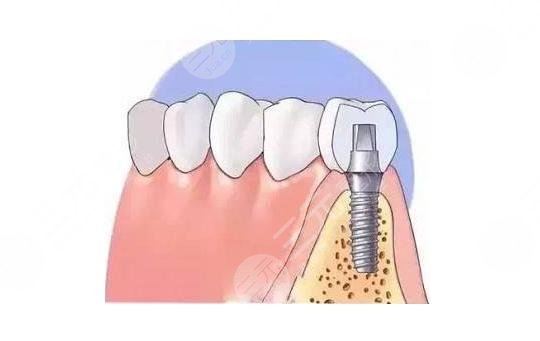

种植牙是目前很多牙齿缺失患者都会选择的一项口腔医疗方式,毕竟牙齿出现缺损的话是很影响一个人的生活质量的,近来就有很多北京的朋友过来咨询北大口腔医院种植牙怎么样?目前来说北大口腔医院在各项口腔服务领域内都是比较专业的一家口腔医院,在北京地区也是很多人信任的医疗机构,在当地有着极好的口碑,而医院在种植牙手术方面技术较为高超,截止目前已经打造了许多成功的案例,下面就给大家具体介绍一下北大口腔医院种植牙怎么样?以及医院种植牙价格表。

种植牙是修复缺失牙的可选,通常价格是在15,000左右的样子,但是具体的价格没有一个固定的标准,受到很多方面的影响。首先因为种植牙的品牌会有所差异,而且在不同的制度方面会存在不同的价格。其次由于每个医院的收费标准不一样,所以不同的医院价格也会存在一定的区别,比如说公立和私立价格就会有所差异。另外每个人的口腔情况不一样,对于一些复杂性的人群而言,种植的数量会更多,而且操作起来会更复杂,因此价格会更昂贵。因此建议大家前往专业的口腔医院进行面诊,明确价格。大致的价格大家可以先参考这个价格表。